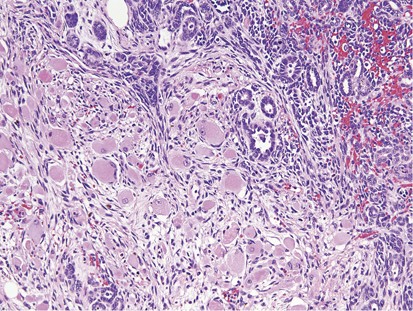

The mass containing the rhabdomyomatous tumors varied from 3.3–17.5 cm with the cut surfaces being solid and cystic, the former varying from tan to yellow to gray and having firm to soft consistencies. On microscopic examination, all of the retroperitoneal lymph-node dissection specimens except for one contained teratomatous elements in addition to the rhabdomyomatous tumors. These included the usual array of interwoven glandular structures, cartilaginous nodules, fibromuscular stroma, and occasional other tissue types. The rhabdomyomatous tumors measured 0.8–5 cm (the two largest estimated from the measured tumor size on the slides and the number of involved slides, see Table 1). They grew as large nodules (Figure 1) to dissecting aggregates (Figure 2) of differentiated rhabdomyocytes, with the former having circumscribed interfaces with the surrounding tissue (Figure 3) and the latter showing peripheral infiltration between teratomatous elements (Figure 4). The cells had either round, regular profiles with centrally placed, spherical nuclei (Figure 5) or elongated, tubular profiles with peripherally placed nuclei (Figure 6). Such myotubes commonly showed nuclear aggregation in a common sarcoplasm (Figure 6) and were identified at least focally in every case. The nuclei showed mild to moderate pleomorphism and had small to moderate-sized nucleoli. Degenerate-type hyperchromasia occurred focally in two cases (Figure 7). Mitotic activity was not seen. In no case was there evident necrosis of the rhabdomyomatous elements. There was no evidence of a primitive, undifferentiated tumor component associated with the rhabdomyocytes.

This rhabdomyomatous tumor dissects among teratomatous glands.

This rhabdomyomatous tumor infiltrates among embryonic-type renal elements.

These round rhabdomyocytes have centrally placed, spherical nuclei and abundant eosinophilic cytoplasm.

This tumor forms numerous myotubes with aggregated nuclei in a common sarcoplasm.